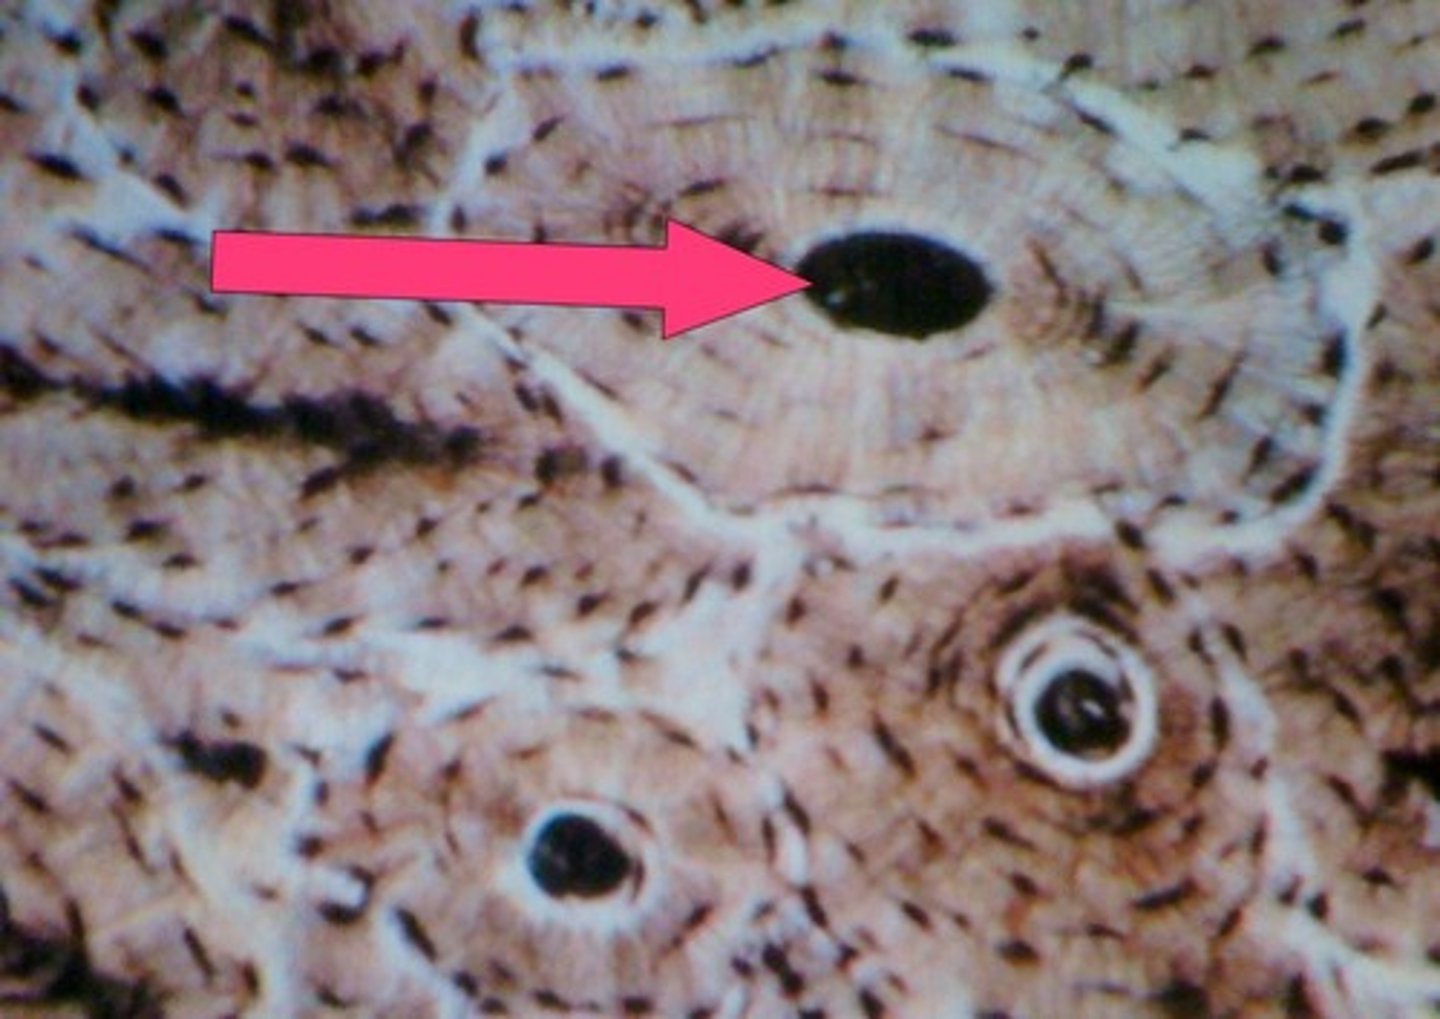

haversian canal

- carries blood vessels

circular inside of osseous tissue